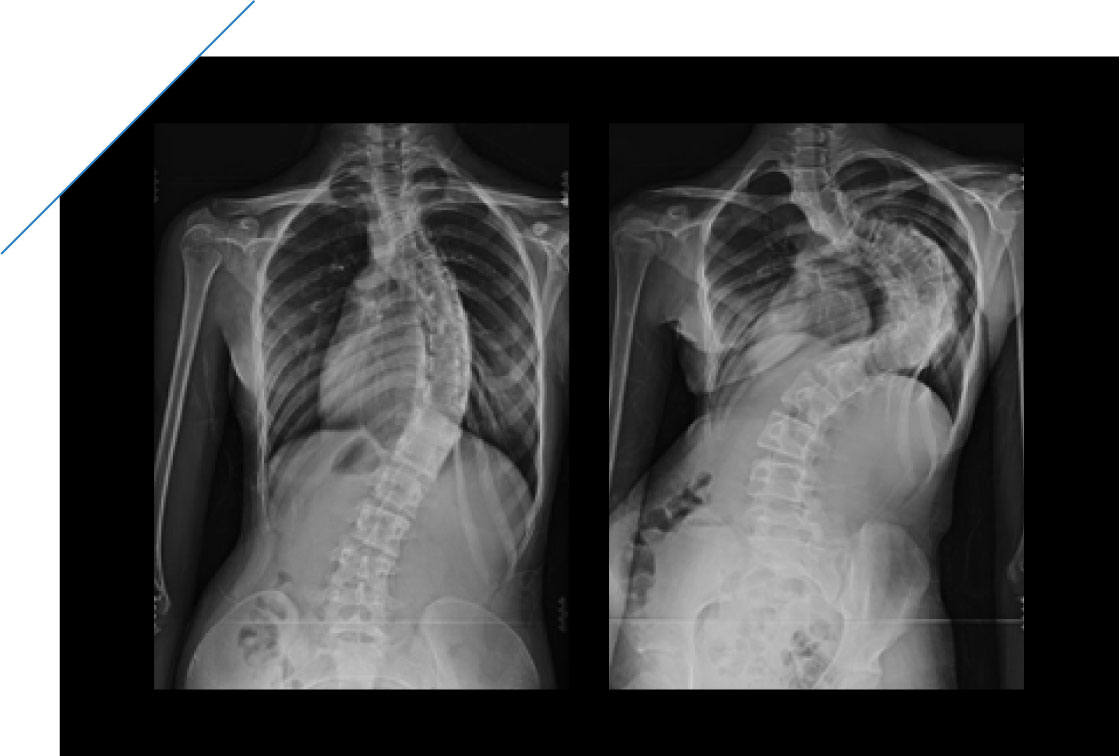

側弯症 軽度 見た目 (307 無料画像)

側弯症 軽度 見た目